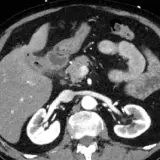

Casos totalmente interactivos con las herramientas que esperaría de un PACS: scroll, ventana, zoom, pan, mediciones, ROI y modo de pantalla completa.

• Anotaciones enlazadas

Anotaciones extensas resaltan los hallazgos clave directamente sobre los casos. Haga clic en los hallazgos enlazados dentro de la descripción del caso para saltar a su ubicación exacta en el estudio.